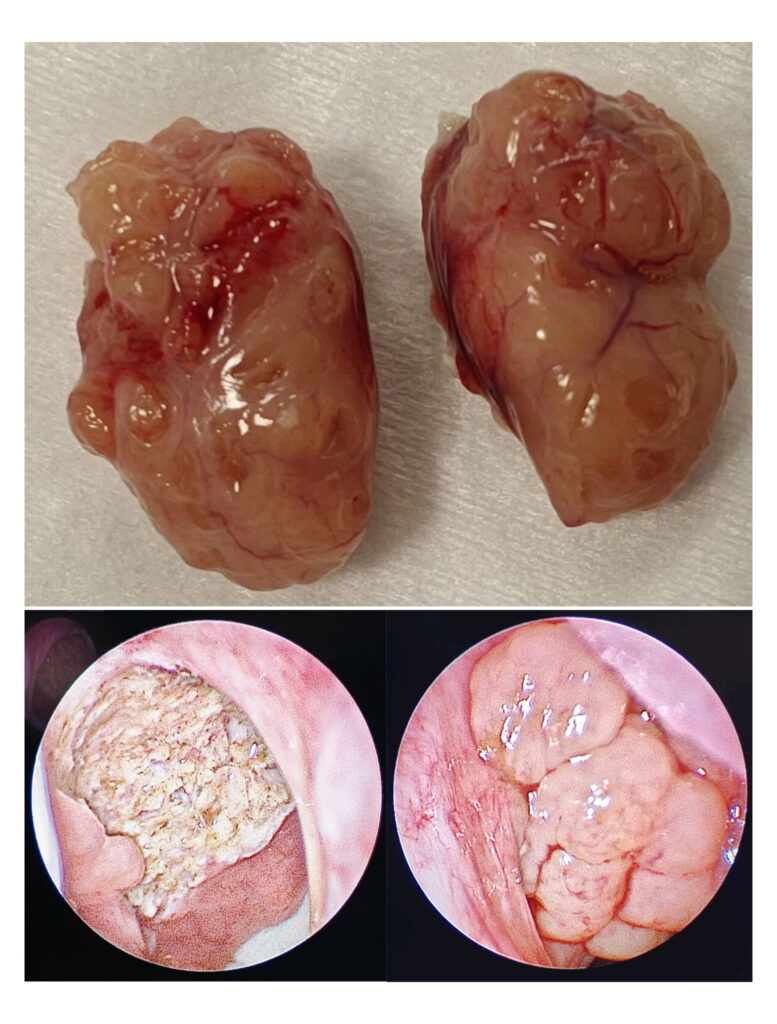

Adenotonsillectomy

Endoscopic Coblation Adenoidectomy

Medtronic BiZact assisted bloodless Tonsillectomy